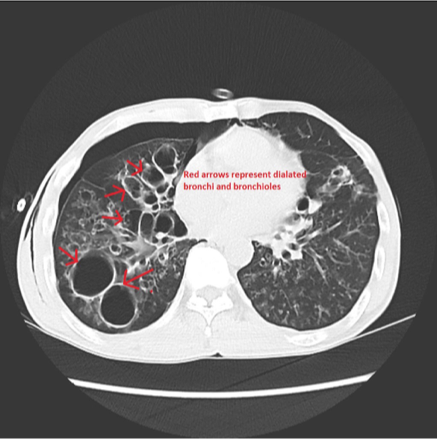

<p>What does this refer to </p>

What does this refer to

Bronchiectasis

What used to diagnose bronchiectasis?

CT Chest IV Contrast

<p>CT Chest IV Contrast</p>